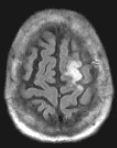

In the brain, it is used to determine hyperacute and acute strokes (detectable from minutes to days). Conventional imaging may not be able to detect hyperacute strokes or differentiate acute from chronic infarcts. With MR diffusion, detection of acute infarcts is immediate and differentiation from old infarcts is obvious.

Routine FLAIR MRI images (left) cannot differentiate between acute infarcts and chronic ischemic changes/infarcts. The diffusion MRI (right) clearly demonstrates an acute infarct in the left frontoparietal region (the chronic changes do not "light up" on the diffusion study).